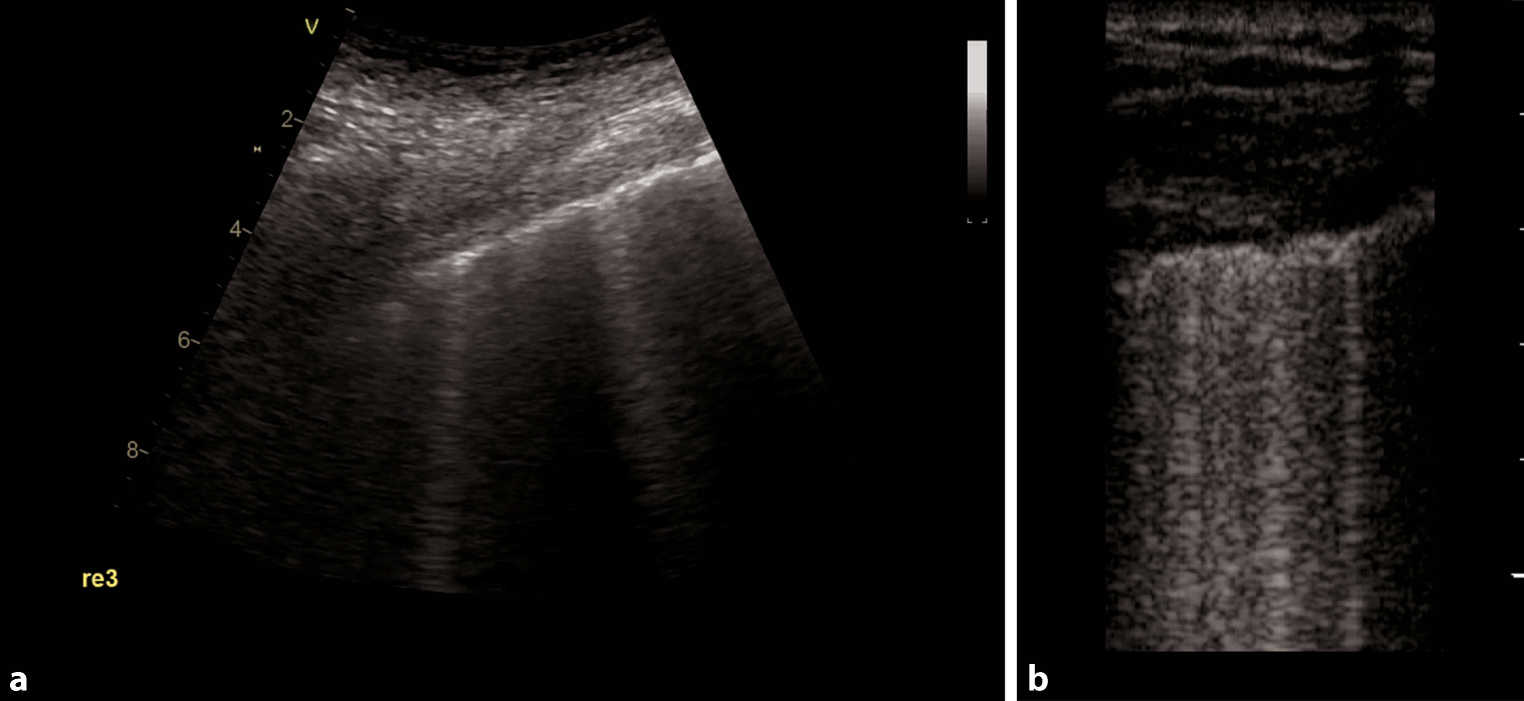

Fig. 9

Evaluation for pleural effusion—right hemithorax. a Schematic of the right sided approach. b Normal sonographic anatomy without pleural effusion

Pleural effusions are reportedly rare in COVID-19 pneumonia, and thus indicate a bacterial superinfection or heart failure [26]. To detect pleural effusions in supine patients, e.g. in an ICU, we recommend scanning the posterior regions with a convex or cardiac transducer as posterior as possible (Figs. 9 and 10). In an upright patient, the posterior regions—zone six (Fig. 8)—can be visualized with a convex or cardiac transducer to identify pleural effusions. In large pleural effusions, compression atelectasis can be visualized. Likewise, as previously mentioned, differential diagnoses of pleural effusions have to be considered [39]. The suspicion of heart failure is further supported by the presence of reverberation artifacts, which arise from a non-fragmented pleural line (B-lines). These B‑lines arise from the smooth pleural line in a bilateral homogenous way, not fading until the end of the screen, moving with pleural sliding and erasing other artifacts (A-lines). The presence and quantity of B‑lines correlate with the severity of clinical presentation of patients [24, 35, 40].